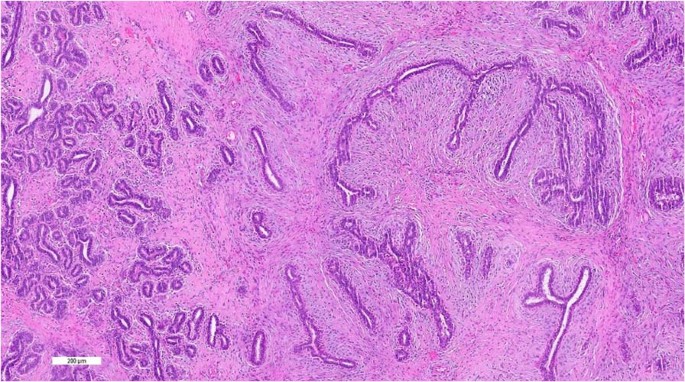

Grossly, the fibroadenoma shows rounded to lobulated, variably encapsulated borders, with fibrous to myxoid cut surfaces. Microscopically, it is a biphasic tumour with circumscribed and pushing contours, composed of an admixture of epithelial and stromal elements, with loss of lobular architecture due to the expansion of stroma between epithelial elements. The pericanalicular growth pattern refers to stromal growth around patent tubules, while the intracanalicular appearance comprises stroma pushing against epithelium creating arc-like epithelial shapes (Fig. 1). Both patterns are often seen in the same lesion, which are without clinical significance, apart from recent recognition that the MED12 mutation is more frequently found in the intracanalicular fibroadenoma [2, 3].